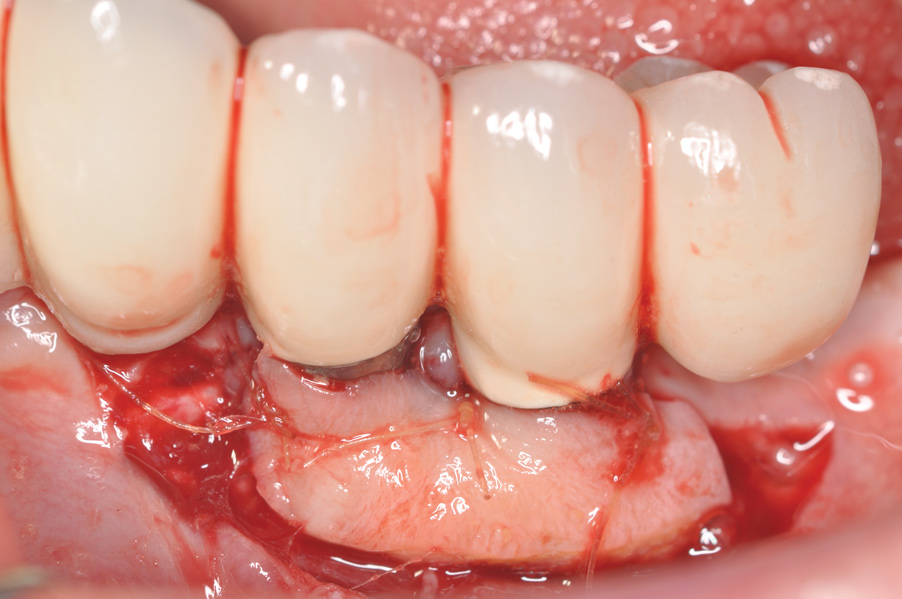

Dental implants have revolutionized the way in which clinicians treat and restore partially and fully edentulous patients and have demonstrated success for managing a broad range of clinical dilemmas. While implants have been highly predictable and have achieved long-term success, they are not immune from complications associated with improper treatment planning, poor surgical and prosthetic execution, material failure, and inadequate or infrequent maintenance. Among these problems are the biologic complications of peri-implant mucositis and peri-implantitis, which are inflammatory conditions in the soft and/or hard tissues surrounding dental implants (Figure 1 through Figure 4).1,2